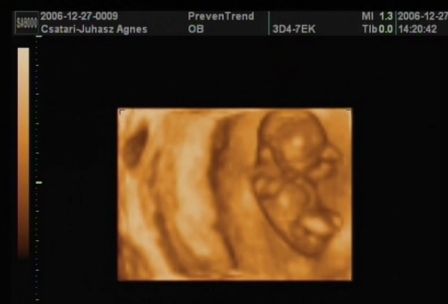

Ma voltam nyaki redő mérésen, integrált teszten. A nyaki redő 0.7 :D

A méretei alapján nem 11 hetes vagyok, hanem kb 1 héttel idősebb.

Rettenetesen ficánkolt, kaptam róla dvd-t is. Boldog vagyok, hogy megörökítettük!!! Hallottam a szive kalapálását és láthattam a kis kezeit, lábait... Velem volt a párom is, gondolhatjátok mennyire boldog volt ő is!

Rakok fel nektek képeket:

Kép Kép Kép Kép